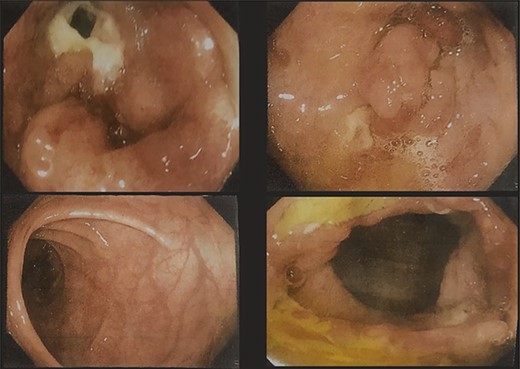

A 51-year-gentlemen and a smoker visited our institute with a history of abdominal pain, predominantly over the umbilical area, constant in nature, associated with anorexia, back pain and occasional chest pain for about 1 year. Besides pallor, other examination findings were grossly normal. His body mass index was 17 mg/m2. The comprehensive blood panel, renal function test and liver function test yielded normal findings. USG of abdomen and pelvis showed thickened cecum and terminal ileum with few adjacent mesenteric lymph nodes likely to be an infective/inflammatory pathology along with coexisting right nephrolithiasis. Intestinal TB was suspected and further investigations were done but reported negative Mantoux test, AFB smear and normal chest X-ray findings. Colonoscopy showed ulcero-proliferative growth in the cecum and descending sigmoid junction with punch biopsy from the cecal growth showing mitotic lesion suggestive of carcinoma colon (Fig. 1). A repeat colonoscopic biopsy of the cecal growth suggested diffuse active colitis. Computed tomography (CT) revealed segmental asymmetrical circumferential mass-like wall thickening of the cecum and ascending colon over the length of 7.6 cm causing luminal narrowing with enhancing soft tissue extension into the adjacent pericolic fat with loss of fat plane with the right psoas major muscle, pericolic fat stranding along with thickening of adjacent peritoneal lining (Fig. 2). The presence of multiple homogeneously enhancing pericolic, ileocolic, superior mesenteric artery and para-aortic groups of lymph nodes suggested colon carcinoma (T4aN2b). It also revealed a small iso-dense lesion showing homogeneous enhancement on the arterial phase in segment VII of the right lobe of the liver abutting capsule suggestive of metastasis. Carcinoembryonic antigen (CEA) was found to be slightly raised (7 ng/dl).

Colonoscopy images showing ulcero-proliferative growth in the cecum and descending sigmoid junction.